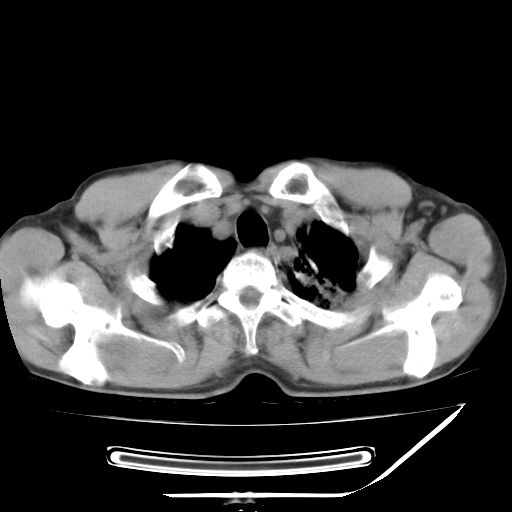

男,59岁,“结核性胸膜炎”30余年,胸部经常疼痛,多次x检查提示“肺部”炎症。腹部疼痛5日,b超提示:“肝内短管结石,余显示不清,建议进一步检查。”

两肺结核并右侧胸腔积液;脾脏、腹腔及腹膜后淋巴结结核[陈旧性];肝内胆管结石

胸部腹部都是结核(双肺。纵隔淋巴结,肝脏,脾脏,肠系膜)

两肺结核并右侧胸腔积液;脾脏、腹腔及腹膜后淋巴结结核[陈旧性];肝内胆管结石。直肠息肉?